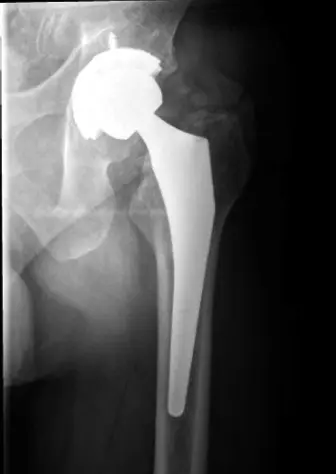

يُعد استبدال مفصل الورك الكلي (THR) إجراءً جراحيًا شائعًا وفعالًا للغاية لتحسين جودة حياة المرضى الذين يعانون من آلام الورك الشديدة وتلف المفصل. ومع ذلك، مثل أي إجراء جراحي كبير، فإنه يحمل مخاطر محتملة، ومن بينها مضاعفة نادرة ولكنها خطيرة تُعرف باسم "شلل العصب الوركي" (Sciatic Nerve Palsy - SNP).

تتراوح نسبة حدوث شلل العصب الوركي بعد استبدال مفصل الورك الأولي من 0.1% إلى 2.8%. ومع ذلك، يمكن أن يرتفع هذا المعدل بشكل ملحوظ في حالات إعادة جراحة مفصل الورك (تصل إلى 7.6%)، أو في الحالات التي تتضمن تشوهات معقدة مثل خلل التنسج النمائي للورك (DDH) الذي يتطلب إطالة كبيرة في الطرف (تصل إلى 11%). تعكس هذه الأرقام أهمية الموضوع لكل جراح عظام، وتؤكد على ضرورة الوعي التام بهذه المضاعفة.